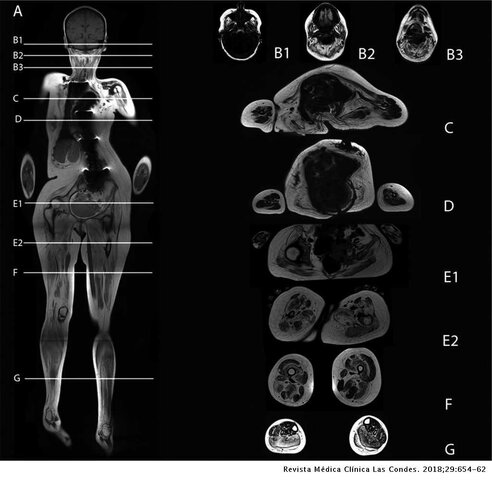

• Resonancia Magnética

Resonancia Magnética

En 1971, el doctor Raymond Damadian demostró que la resonancia magnética podía ser usada para detectar enfermedades. Pero fue en 1972 cuando creó el primer equipo de este.

M. A. Foster, J. M. S. Hutchison, J. R. Mallard y M. Fuller fueron de los primeros en demostrar que podía medirse con precisión la composición corporal, a través de imágenes por resonancia magnética.